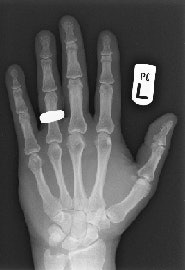

This digital radiograph of Dr. Adrian Thomas' own hand was taken on 8 November 2005, 110 years after the discovery of x-rays. All images courtesy of Dr. Adrian Thomas.